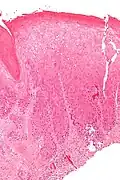

| Micrograph of (classic) vulvar intraepithelial neoplasia III. H&E stain. | |

Micrograph of vulvar intraepithelial neoplasia III. H&E stain.